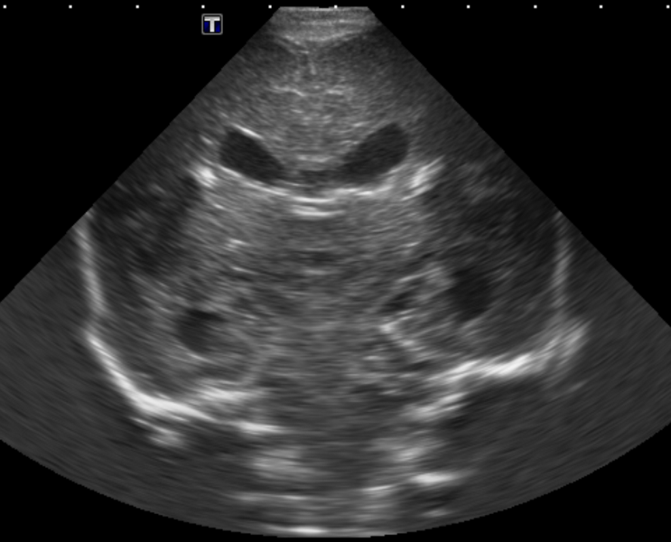

Section 1 Submit Findings Case149 Findings Brain The brain is immature. Yes No There is under-sulcation and open sylvian fissures. Yes No There is/are multiple hypoechoic areas in the periventricular white matter. Yes No There is/are multiple hyperechoic areas in the periventricular white matter. Yes No There is diffuse cerebral edema with diffusely increased echogenicity of the brain parenchyma and loss of grey white matter differentiation. Yes No The thalami/basal ganglia are hypoechoic. Yes No There is periventricular calcification. Yes No There is intra-parenchymal calcification. Yes No CSF spaces/ventricular system There is a prominence of the extra axial fluid spaces. Yes No There are debris/septations in the extra axial fluid spaces. Yes No There are debris/septations in the ventricles. Yes No There is a subdural collection on the right/left side. Yes No There is prominence of the ventricular system. Yes No There is an asymmetry of the ventricular system. Yes No There is a cavum septum pellucidum. Yes No There is a midline shift towards right/left. Yes No The choroid plexus is bulky/lobulated. Yes No There is a choroid plexus cyst measuring… Yes No There are debris/clots in the occipital horn. Yes No There is a posterior fossa cyst measuring… Yes No The tentorium is elevated/depressed. Yes No The lateral ventricle/s are dilated. Yes No The third ventricle is dilated. Yes No The 4th ventricle is dilated. Yes No There are pseudo cysts. Yes No Germinal matrix hemorrhage (Only in the premature infants): Please do not answer if the patient is a full term. There is a germinal matrix hemorrhage, consistent with a grade I hemorrhage. Yes No There is an intraventricular extension consistent with a grade II hemorrhage. Yes No There is an intraventricular extension with the dilatation of ventricles, consistent with a grade III hemorrhage. Yes No There is an intra-parenchymal extension, consistent with grade IV hemorrhage. Yes No On color Doppler examination, the Resistive index in the anterior cerebral artery is… There is a loss of the diastolic flow on the Doppler exam. Yes No There is altered vascularity on Doppler imaging. Yes No There is an AVM in the region of… Yes No